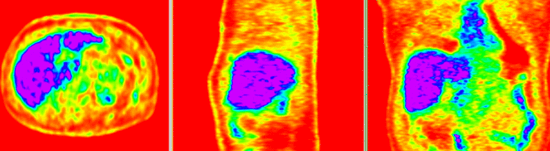

this is the fixed CT image. All images are aligned into this space this is the fixed PET image. All images are aligned into this space lleft this is the moving image. The transform is calculated by matching this to the reference image this is the moving image. The transform is calculated by matching this to the reference image

fixed image/target fixed image/target moving image moving image

• reference/fixed : baseline CT: 0.97 x 0.97 x 3.27 mm , 512 x 512 x 267; PET: 4.7 x 4.7 x 3.3 mm , 128 x 128 x 267

• moving: CT: 0.98 x 0.98 x 5, 512 x 512 x 195; PET: 4.1 x 4.1 x 5 mm, 168 x 168 x 195